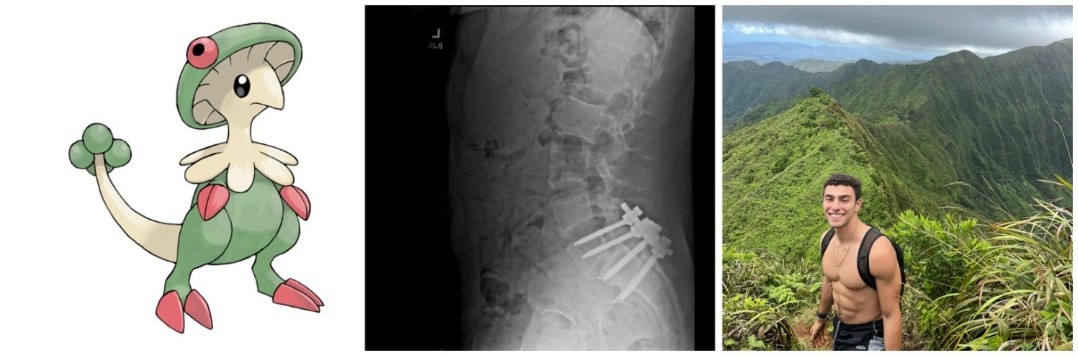

网友们涌入他的社交媒体寻找答案。首先看到的就是他的推特背景,是宝可梦斗笠菇、他的脊柱CT、和一张腹肌照……

(他的推特背景)

当时他出现了一些背部疼痛的症状,Martin回忆:“他的脊椎有点错位,他跟我说他的下椎骨错位了几乎半英寸,我觉得可能挤压到了神经。”

总之在Surfbreak住了大约半年后,Mangione就回到了东海岸,跟Martin说是去检查身体,做背部手术。8月,Martin通过短信联系他,问他身体怎么样了,Mangione给他发来了一些照片,是他脊椎的CT片。

扭曲的脊椎上插满了巨大的螺丝钉,让Martin感到很震惊,他紧接着追问,“你感觉怎么样?”